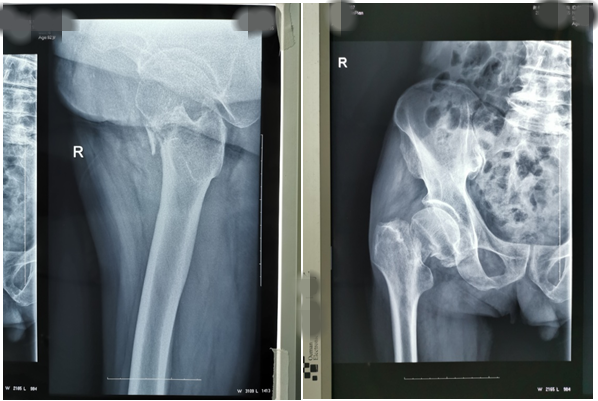

近期,我科又為兩位高齡老人因股骨頸骨折行髖關節(jié)置換術。一位是呂大爺,82歲高齡,右髖部外傷后疼痛一個月就診。當時呂大爺外傷后局部疼痛,未引起注意仍日?;顒?,癥狀逐漸加重后就診,既往有高血壓、腦梗塞、腦出血病史,入院后積極完善術前評估,在無絕對手術禁忌癥時行右側股骨頸骨折髖置換術,手術時間短,出血少,術后第二天呂大爺扶助步器下床活動,避免了因骨折長時間臥床各種并發(fā)癥的發(fā)生,老人及家屬對我們的治療非常滿意。(見下圖)

右髖正側位手術前后對比圖